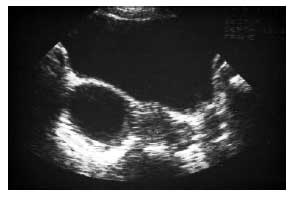

Classically, it is carried out by a suprapubic approach with a full bladder, which allows study not only of the cyst but of all the internal genital organs. An analysis of the cyst itself indicates the size, shape and even volume by measurement of the three diameters, the thickness and regularity of the wall and the nature of the cyst content. An anechogenic, purely liquid image with a thin, regular wall is in favor of a functional cyst (fig. 1, 2). Volume measurement is a basis for surveillance and for the decision of possible needle aspiration.

Fig. 1. Functional cyst of the right ovary: purely fluid appearance, anechogenic and homogeneous with a thin, regular wall.